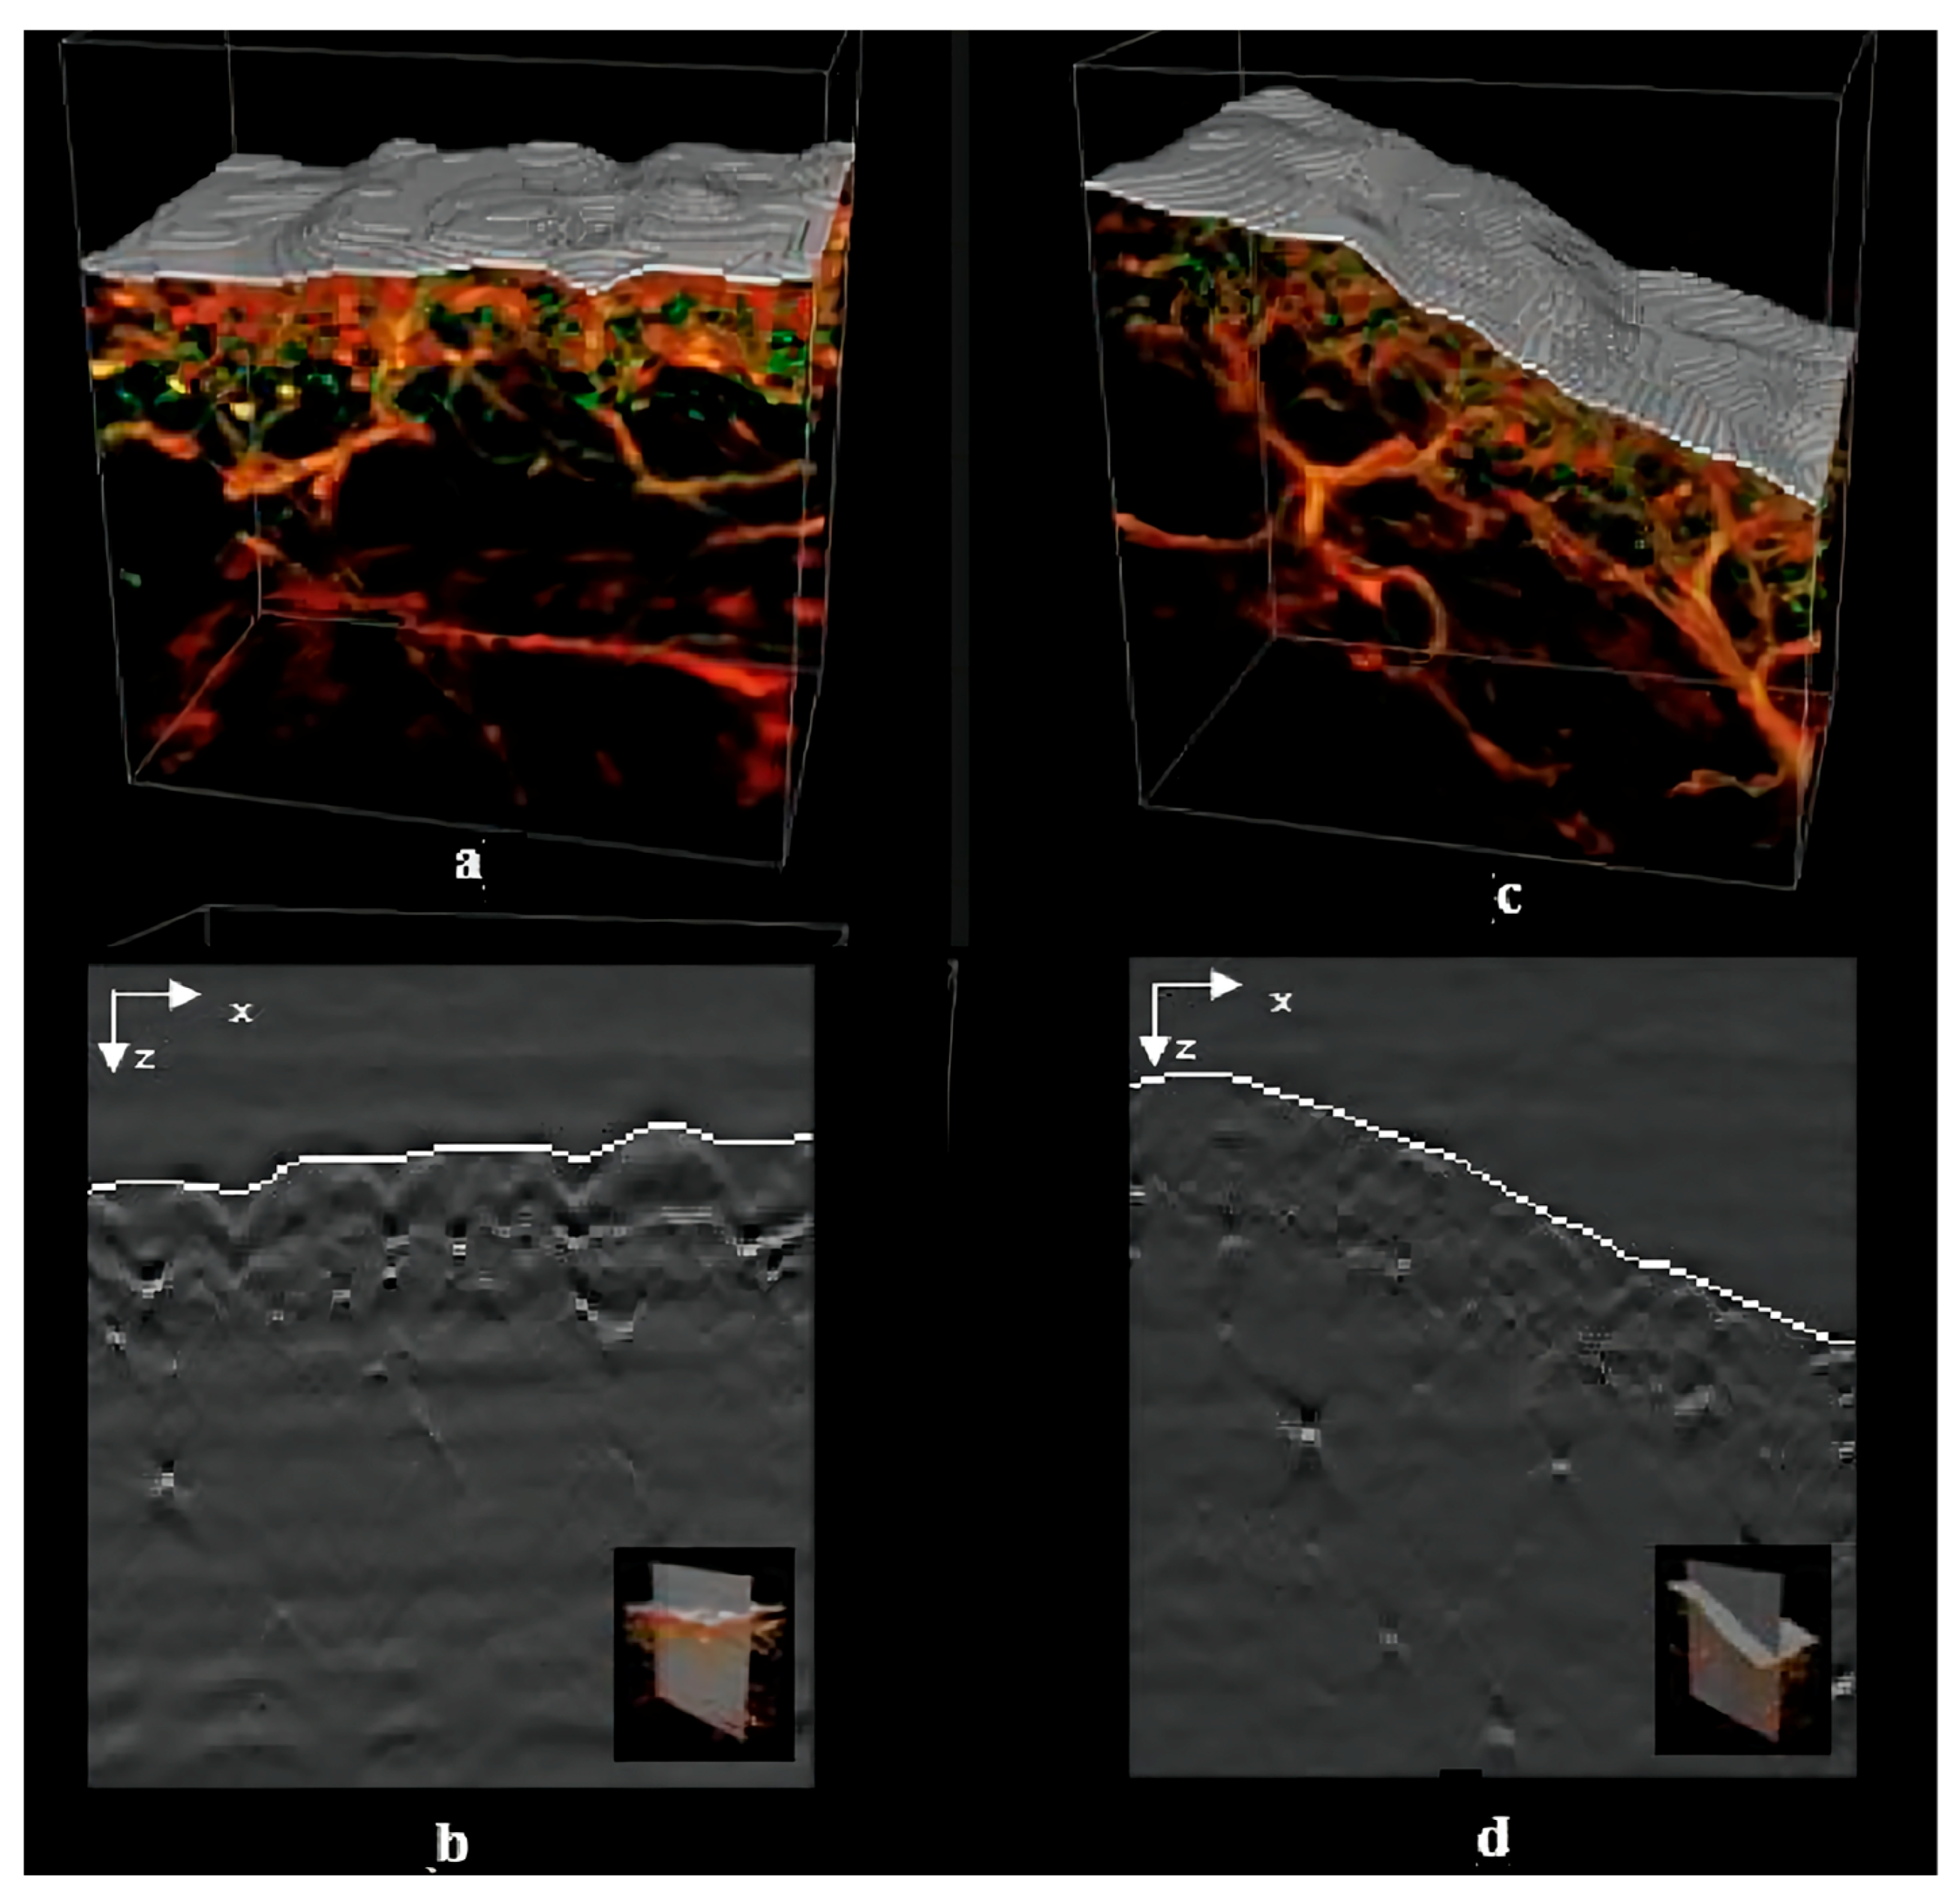

- Nitkunanantharajah, S.; Zahnd, G.; Olivo, M.; Navab, N.; Mohajerani, P.; Ntziachristos, V. Skin Surface Detection in 3D Optoacoustic Mesoscopy Based on Dynamic Programming. IEEE Trans. Med. Imaging 2020, 39, 458–467. [Google Scholar] [CrossRef]

| RSOM | 1.5–5 mm | Light absorption | Qualitative Non-invasive | Longer scan times | Observation of vascular structures | [86] |